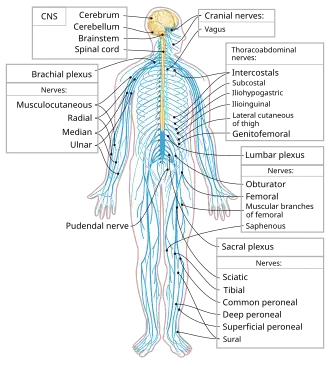

The spinal cord is a long, thin, tubular structure made up of nervous tissue that extends from the medulla oblongata in the lower brainstem to the lumbar region of the vertebral column (backbone) of vertebrate animals. The center of the spinal cord is hollow and contains a structure called the central canal, which contains cerebrospinal fluid. The spinal cord is also covered by meninges and enclosed by the neural arches. Together, the brain and spinal cord make up the central nervous system.

The spinal cord functions primarily in the transmission of nerve signals from the motor cortex to the body, and from the afferent fibers of the sensory neurons to the sensory cortex. It is also a center for coordinating many reflexes and contains reflex arcs that can independently control reflexes.[1] It is also the location of groups of spinal interneurons that make up the neural circuits known as central pattern generators. These circuits are responsible for controlling motor instructions for rhythmic movements such as walking.[2]

The spinal cord is continuous with the caudal portion of the medulla, running from the base of the skull to the body of the first lumbar vertebra. It does not run the full length of the vertebral column in adults. It is made of 31 segments from which branch one pair of sensory nerve roots and one pair of motor nerve roots. The nerve roots then merge into bilaterally symmetrical pairs of spinal nerves. The peripheral nervous system is made up of these spinal roots, nerves, and ganglia.

Segments

There are 31 spinal cord nerve segments in a human spinal cord:

- 8 cervical segments forming 8 pairs of cervical nerves (C1 spinal nerves exit the spinal column between the foramen magnum and the C1 vertebra; C2 nerves exit between the posterior arch of the C1 vertebra and the lamina of C2; C3–C8 spinal nerves pass through the intervertebral foramen above their corresponding cervical vertebrae, with the exception of the C8 pair which exit between the C7 and T1 vertebrae)

- 12 thoracic segments forming 12 pairs of thoracic nerves

- 5 lumbar segments forming 5 pairs of lumbar nerves

- 5 sacral segments forming 5 pairs of sacral nerves

- 1 coccygeal segment

- Cervical enlargement – corresponds roughly to the brachial plexus nerves, which innervate the upper limb. It includes spinal cord segments from about C4 to T1. The vertebral levels of the enlargement are roughly the same (C4 to T1).

- Lumbar enlargement – corresponds to the lumbosacral plexus nerves, which innervate the lower limb. It comprises the spinal cord segments from L2 to S3 and is found about the vertebral levels of T9 to T12.

Spinal cord in the nervous system

Spinal cord in the nervous system -